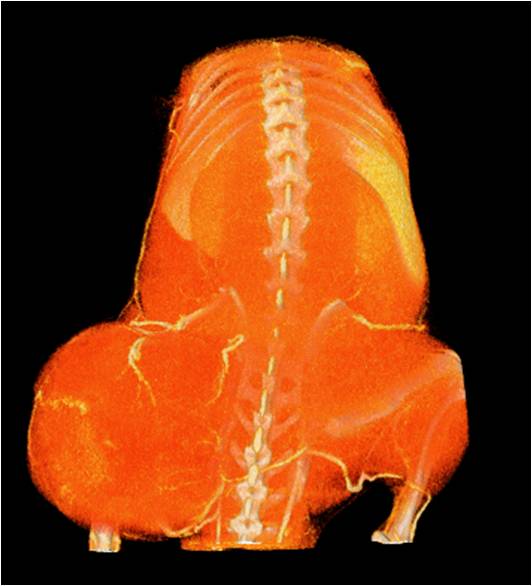

ChiPet 100是一款針對離體骨,小鼠,大鼠及兔子等動(dòng)物進(jìn)行多功能3D掃描的Micro-CT系統。

可以測量骨參數、棕色脂肪、皮下脂肪、脂肪肝、血管、腫瘤轉移等參數。

能進(jìn)行全身血管成像研究,獲得高分辨率的血管造影影像;

檢測案例

腫瘤血管生成

肺轉移

小鼠模式,22.5μm像素

正常

8天 14天

無(wú)造影劑注入 造影劑注入

心血管

胸部和心血管的層析成像 胸部和心血管的3D圖像